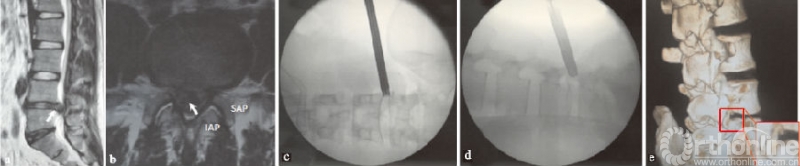

后外侧区突出是最常见的腰椎间盘突出症类型,其突出区域在于侧隐窝及椎弓根区(见图2a-b)。基于行走根的解剖位置,单纯的椎弓根区一般不引起症状;但在侧隐窝区,即使大米粒状的突出,都可以引起相对剧烈的下肢放射痛。

(a)(b)L4/5节段后外侧区突出的矢状位和横断位;(c)(d)工作通道放置X线透视图;↖指突出椎间盘,IAP指下关节突,SAP指上关节突

图2 MRI示L4/5节段后外侧椎间盘突出及置管图